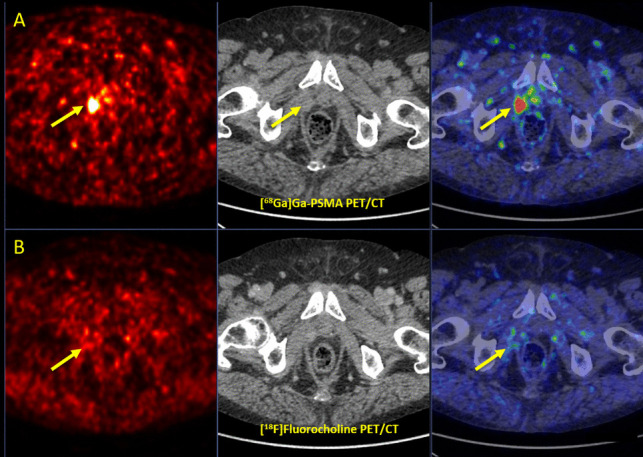

Results: Both imaging modalities detected 136 total malignant lesions. [68Ga]Ga-PSMA-11 and [18F]FCH PET/CT detected 125 and 60 lesions with a sensitivity of 96% and 48%, respectively. Tumor-to-background ratios and semi-quantitative PET parameters on [68Ga]Ga-PSMA-11 were significantly higher in 54 (41.2%) tracer-avid congruent lesions detected on both imaging modalities. [68Ga]Ga-PSMA-11 PET/CT exclusively detected 71 (52.2%) lesions, while 6 (4.4%) lesions were solely seen on [18F]FCH PET/CT. [68Ga]Ga-PSMA-11 and [18F]FCH PET/CT were positive in 35/46 (76%) and 26/46 (57%) patients, respectively. PET/CT imaging led to a major treatment change in 4 (8.7%) patients, of which [18F]FCH PET/CT had superior impact in one patient.

Conclusions: [68Ga]Ga-PSMA-11 PET/CT revealed superior diagnostic performance to [18F]FCH PET/CT in patients with recurrent PCa, specifically with very low PSA levels ≤ 1 ng/ml. Moreover, it led to more accurate staging and clinical management of the disease. [18F]FCH PET/CT may play a complementary role in rare, select high-risk cases with negative [68Ga]Ga-PSMA-11 PET/CT and ongoing ADT.